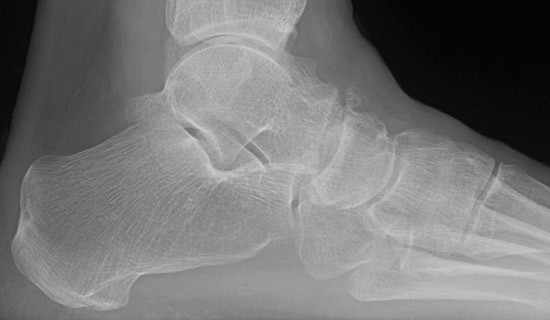

El estudio de imagen con rayos X es suficiente para identificar el problema y confirmar el diagnóstico de la artrosis Astrágalo Escafoidea. Es recomendable la realización de radiografías dorsoplantar, lateral y oblicuas de los pies, las dos primeras proyecciones en carga.

Rx Lateral. Artrosis Astragalo-escafoidea

Radiografía Lateral. Artrosis Astragalo-escafoidea